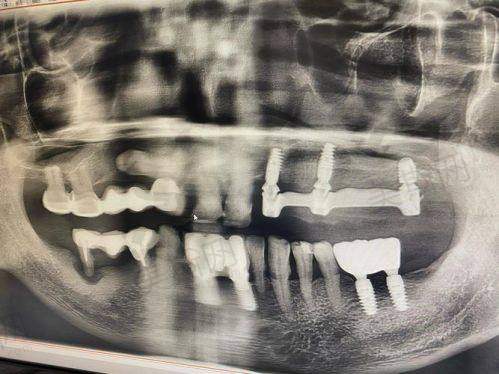

在技术实力上,医院以“数字化种植”和“个性化正畸”为核心优势,其3D导航种植技术可精细避开神经血管,单颗种植手术30分钟内完成,骨结合率超98%;隐形矫正技术通过数字化方案设计,缩短矫正周期30%,患者口碑评价“成效自然、周期短”。医生团队由种植修复硕士、正畸核心骨干医生领衔,累计完成超万例口腔诊疗实例,其中复杂半口/全口种植、疑难正畸病例成功几率达99.6%。

医院引进德国3D导航种植系统,通过CBCT扫描生成口腔三维模型,医生在计算机引导下精细规划种植体角度、深度及位置,术中实时导航避免神经血管损伤,实现“可视化种植”。该技术适用于单颗、多颗及半口/全口缺牙,尤其对牙槽骨条件差(如骨量不足、骨质疏松)患者,可通过数字化导板精细植入,减少创伤,术后肿胀轻、修复快。

- 精细度高:误差≤0.5mm,避免传统种植“盲种”风险;

- 微创效率高:切口仅3 - 5mm,单颗种植30分钟完成,当天即可戴临时牙冠;

- 适应症广:支持即刻负重(拔牙后立即种植,当天咀嚼软食),半口种植仅需4 - 6颗植体,费用降低30%。

擅长领域:复杂半口/全口种植、即刻负重技术、骨增量手术(如植骨、上颌窦提升)、全口牙缺失修复

技术亮点:累计完成超3000例种植牙手术,尤其擅长牙槽骨重度吸收、高龄患者(80岁以上)种植修复,创举“微创骨增量+即刻负重”联合技术,解决传统种植“周期长、创伤大”难题。患者评价:“姚医生方案细致,手术稳,半口牙种完当天就能吃粥,复查时导医全程陪同,特别省心。”